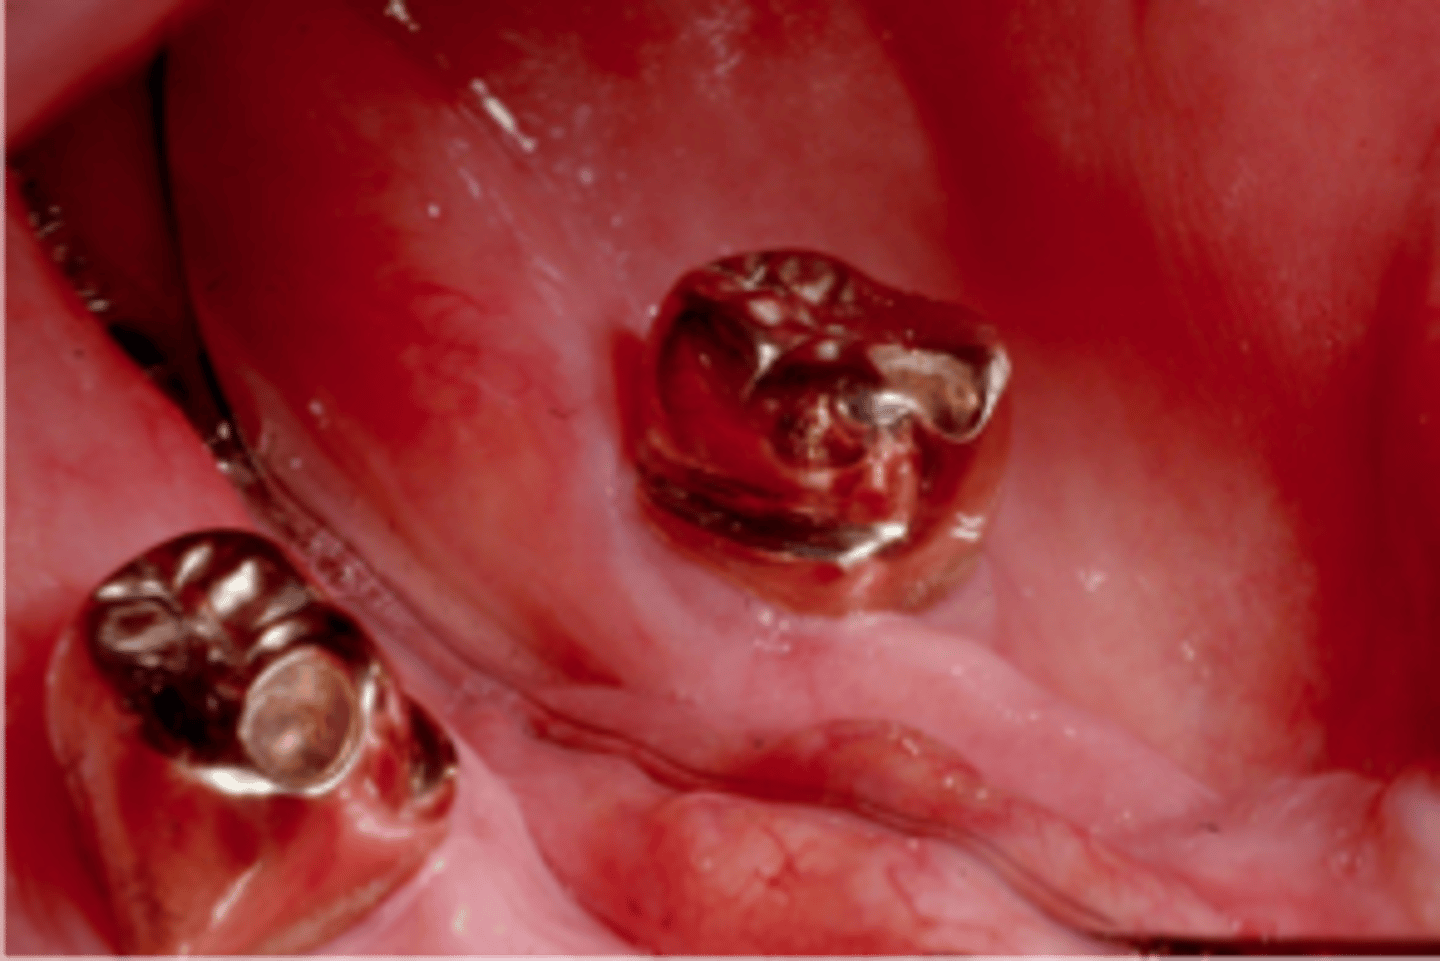

survey crowns

This gold crown serves as an RPD abutment. The milled lingual ledge optimizes reciprocation and allows the bracing arm to restore normal lingual contour when the RPD is fully seated. The bracing arm would be less noticeable to the patient.